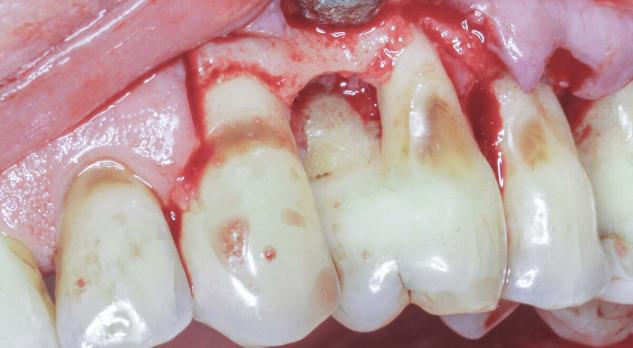

Chirurgie kan na een initiële parodontale behandeling noodzakelijk zijn om verdere pocketdieptereductie te realiseren. In deze nascholing leert u wanneer een chirurgische benadering zinvol is en welke patiëntgebonden en lokale factoren bepalend zijn voor het behandelresultaat. Denk aan mondhygiëne, rookgedrag, medicatiegebruik, maar ook aan anatomische kenmerken op gebitselementniveau.

De nascholing behandelt twee hoofdbenaderingen: resectief en regeneratief. U krijgt inzicht in de verschillen tussen beide strategieën en leert welke technieken en materialen daarbij toegepast worden. Ook wordt er aandacht besteed aan flapsluiting, waarbij de positionering afhankelijk is van de gekozen chirurgische benadering.

Verder komt postoperatieve zorg aan bod, waaronder wondverzorging, pijnbestrijding en nazorginstructies voor de patiënt. U leert hoe u complicaties herkent en wat u kunt doen bij veelvoorkomende problemen zoals nabloeding, perforatie of botsekwesters.

Deze nascholing biedt praktische handvatten om chirurgische parodontale behandelingen goed te indiceren, voor te bereiden, uit te voeren en op te volgen.